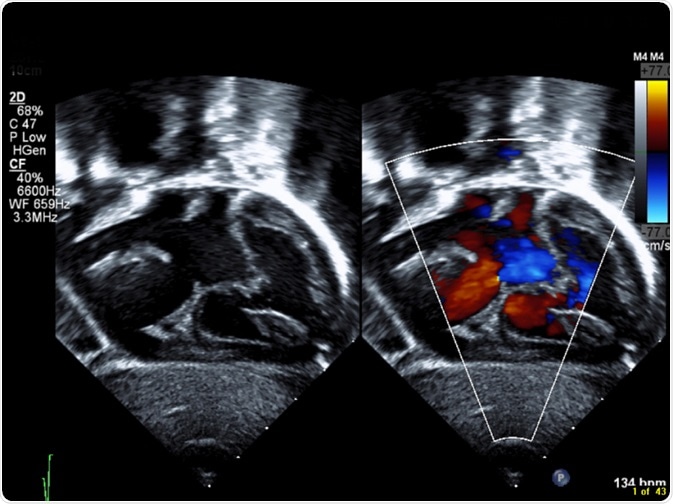

Congenital heart disease (CHD) is a broad term, which is used to describe several cardiac defects that may be found at birth, and affects proper heart function to varying degrees.

CHD is the most prevalent inborn disorder found in new-born babies, and it is the main cause of death from congenital birth defects in the perinatal period and during infancy. It is estimated that CHD may occur in up to as many as 13 in every 1000 live births, and mortality, as well as morbidity, are largely dependent on early diagnosis and timely transfer to specialized institutions with the necessary capacity to treat these conditions.

CHD may present with an array of signs and symptoms, some of which may be apparent immediately after birth, and others may not be until later in childhood or even early adulthood. Among these signs and symptoms is a cyanotic appearance, which is a bluish tinge to the skin, due to inadequate oxygen flow throughout the tissues.

Additionally, the infant may have an extraordinary fast heartbeat with a corresponding fast rate of breathing. There may be noticeable swelling around the eyes, abdomen, or legs. These children generally thrive very poorly in comparison to their peers. In older children and young adults, there may a constant complaint of fatigue, unusual tiredness, and respiratory difficulties.

Although there are many different CHDs, they may be grouped into CHDs that cause septal defects, narrowing of the aorta, narrowing of the pulmonary valve, transposition of the main vessels of the heart, and underdevelopment of the heart.

Septal defects are colloquially known as “holes” in the heart. These arise when there are abnormal connections between any of the heart’s chambers, which normally only communicate via a system of valves that open and close with contraction of the heart.